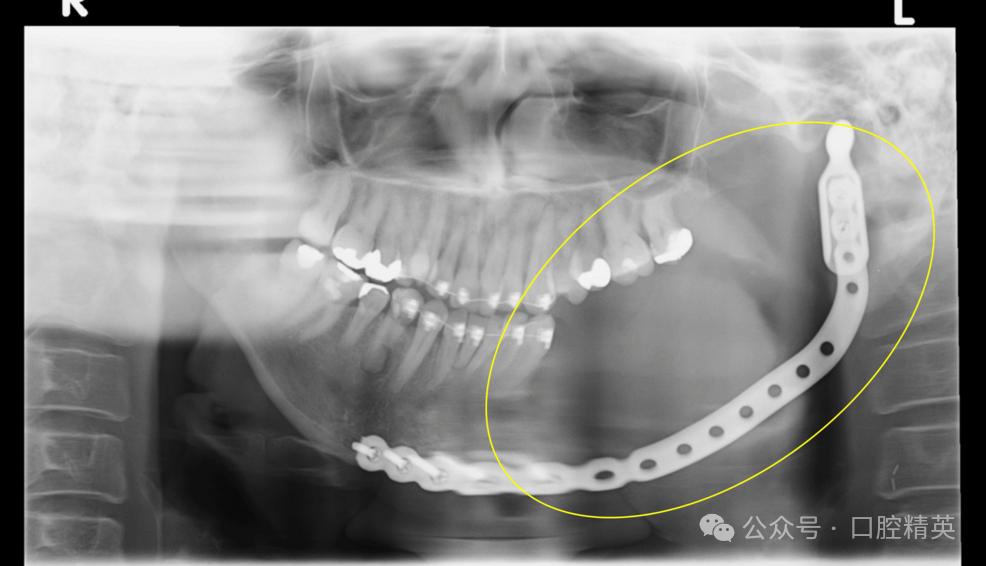

超声检查未发现颈部淋巴结转移征象。氟代脱氧葡萄糖F18正电子发射断层扫描(PET)显示,拔牙窝至左侧下颌支区域肿块呈高摄取(图8),未发现提示远处转移的异常摄取。

图8:38牙拔除术后氟代脱氧葡萄糖F18正电子发射断层扫描

氟代脱氧葡萄糖F18正电子发射断层扫描显示,拔牙窝至左侧下颌支区域肿块呈高摄取(黄色椭圆:高度提示恶性)。

结合上述检查结果,患者被诊断为原发性骨内癌(PIOC),并于2017年8月接受左侧颈淋巴结清扫术、左侧半下颌骨切除术,并行钛板联合腹直肌游离皮瓣修复(图9)。

图9:术后全景片(黄色椭圆:病变区域已完整切除)